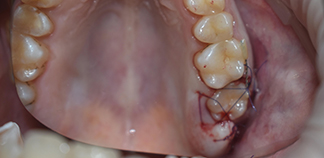

До лечения

Пришли с жалобой на сколотый зуб.

Пациенту 17 лет.

Как лечили

Удален сколотый седьмой зуб. Проведена аутотрансплантация восьмого зуба в подготовленную лунку. Через три месяца жалоб от пациента не поступило.